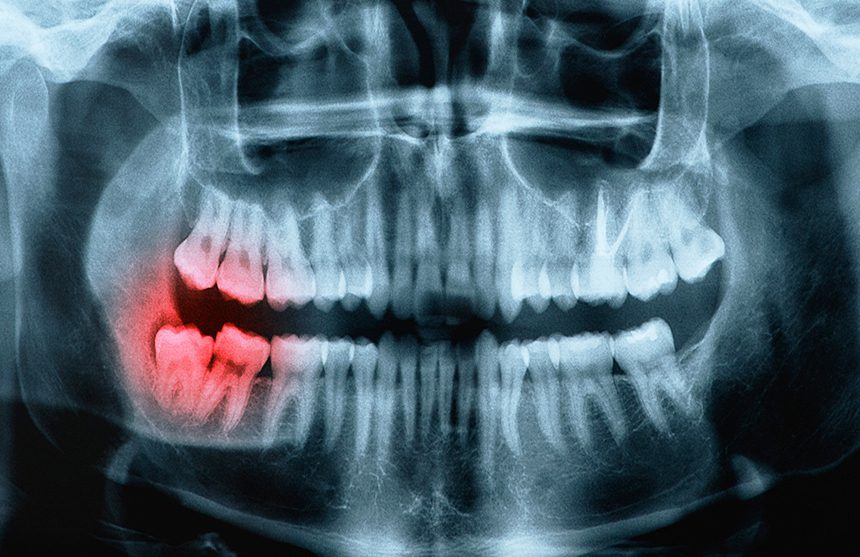

Wisdom Teeth Extractions

Third molars, commonly referred to as wisdom teeth, generally make their appearance between the ages of 17 to 25. Wisdom teeth extractions can be performed because of an active problem such as pain, swelling, decay or infection, or as a preventative measure to avoid serious problems in the future.

Wisdom teeth removal is a common procedure, that can be performed under local anesthesia, intravenous (IV) sedation, or oral sedation by a specially trained dentist in a certified surgery office.

The surgery does not require an overnight stay, and you will be released with post-operative instructions and medication (if necessary), to help manage any swelling or discomfort.

While not all wisdom teeth require removal, in most cases, inadequate space in the mouth prevents wisdom teeth from properly coming in or being fully functional. When this happens, the tooth can become impacted, or stuck, in an undesirable or potentially harmful position. If left untreated, impacted wisdom teeth can contribute to infection, damage to other teeth, and can possibly cause cysts or tumors.